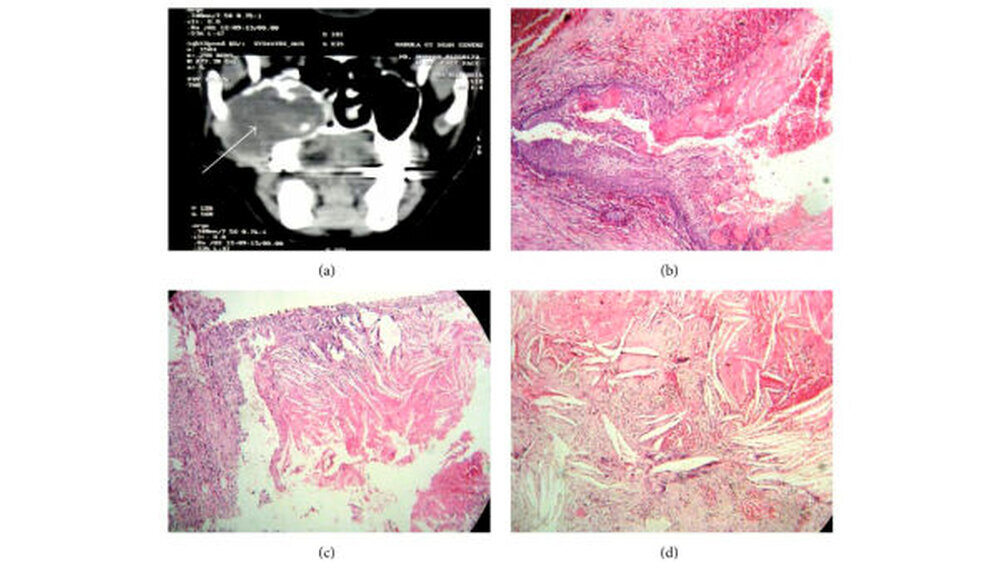

Klinisch zeigte sich eine weiche Schwellung, die vom Vestibulum bis zur Mittellinie des harten Gaumens reichte. In der Computertomografie ließ sich eine abgegrenzte-osteolytische Veränderung nachweisen, die sich bis in den ipsilateralen Sinus maxillaris erstreckte. Bei Verdacht auf Vorliegen eines keratozystischen odontogenen Tumors (KCOT) wurde die Raumforderung enukleiert und histopathologisch untersucht. Hier konnte bei Vorliegen von Fremdkörperriesenzellen, Blut und Cholesterinkristallen die Diagnose einer kalzifizierenden odontogenen Zyste mit einem Cholesterolgranulom getroffen werden (Abbildung 1).